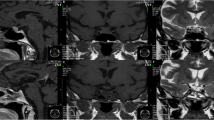

Preoperative magnetic resonance imaging (MRI) studies of the patients were also retrospectively analyzed. Available MRI studies of the sellar region were performed with 3 mm scans in sagittal and coronal planes and included T1-weighted sequences, T1-weighted images after administration of gadolinium (Gd) and T2-weighted images. Maximum tumor diameter and location of sellar lesion as well as the post-contrast enhancement pattern were assessed.

On the preoperative MRI, the tumor diameter ranged between 11 and 25 mm. In two cases, a parasellar extension of the tumor was observed. All lesions enhanced either homogenously or heterogeneously after Gd administration. None the MRI findings, summarized in Table 2, proclaimed the presence of a collision sellar lesion, so that in every case the preoperative diagnosis was a pituitary adenoma (Figs. 6, 7).